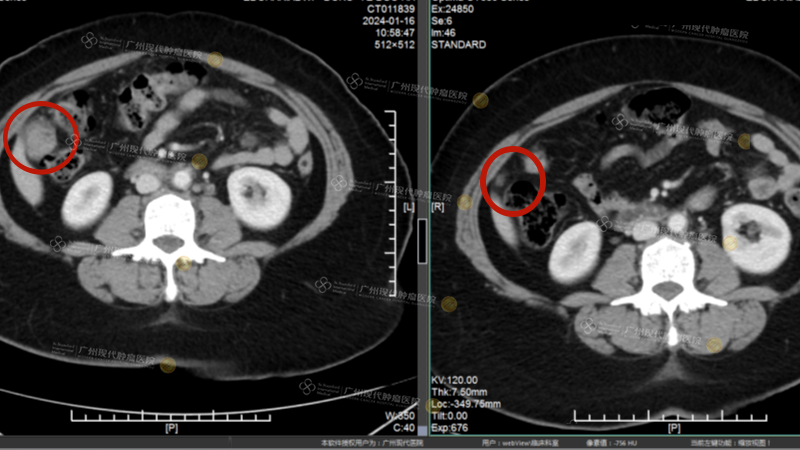

Điều khiến tôi càng bất ngờ và vui mừng hơn nữa là trong quá trình điều trị toàn diện xâm lấn tối thiểu, cơ thể tôi vẫn luôn trong tình trạng tốt; tôi vẫn có thể làm việc, sinh hoạt bình thường. Sau 2 đợt điều trị, đội ngũ MDT giải thích kết quả thăm khám cho chúng tôi: khối u trong bụng đã giảm rõ rệt, khiến gia đình chúng tôi yên tâm và có động lực tiếp tục điều trị! Trước khi điều trị, chỉ số khối u của tôi là 1352,7 lng/ml. Sau hai đợt điều trị, chỉ số khối u giảm nhanh chóng chỉ sau một tháng và hiện ở mức bình thường. Đến nay, khối u ở bụng đã “biến mất”, các triệu chứng như chảy máu âm đạo bất thường cũng không còn nữa.

Ảnh trái: Chụp ngày 16/1/2024, các khối u ở khoang bụng trước khi điều trị

Ảnh phải: Chụp ngày 10/6/2024, các khối u ở khoang bụng hầu như “biến mất” sau khi điều trị